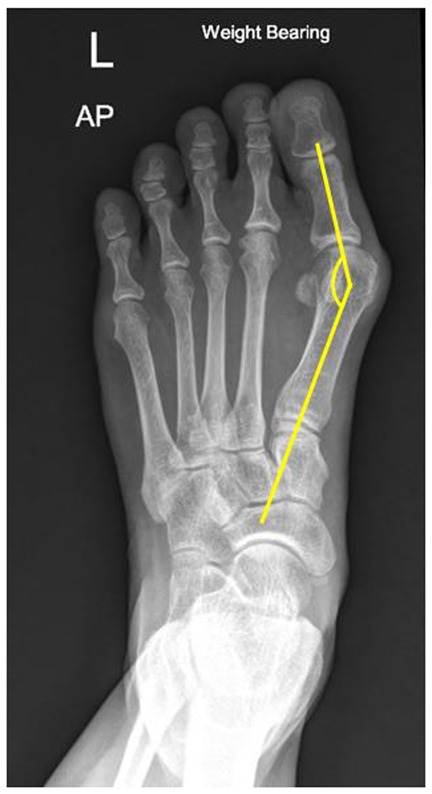

2. Hallux valgus angle (HVA): The centres of the proximal and distal metaphyseal–diaphyseal areas of the proximal phalanx of the hallux were marked as the axis of the bone. The intersection of the 1st metatarsal and hallux proximal phalanx axes was defined as the HVA. An HVA of less than 15 degrees was considered normal (4) (Figure 2).

Figure 2

X-ray of a left foot in anteroposterior (AP) view. It shows bone structures with a yellow line indicating an angled path from the proximal phalanx of big toe to the first metatarsal bone, indicating angle of big toe or bunion.

Figure 2. Illustration of HVA measurement in the weight-bearing plain film; the centres of the proximal and distal metaphyseal–diaphyseal areas of the proximal phalanx of the great toe were marked as the axis of the bone. The intersection of the 1st metatarsal and great toe proximal phalanx axes was defined as the hallux valgus angle.